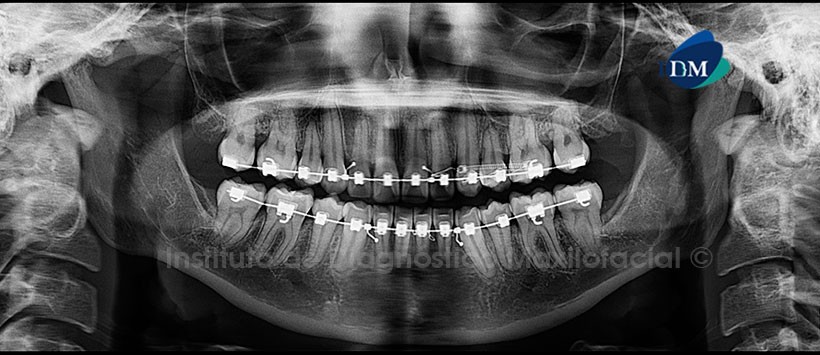

Paciente de 20 años de edad acude al Instituto de Diagnostico Maxilofacial para evaluación de las piezas dentarias por motivo de ortodoncia.

A la evaluación panorámica (ortopantomografia), se aprecia neumatizacion alveolar de ambos senos maxilares, aparatología fija para ortodoncia bimaxilar, ausencia de terceras molares y pre molares (con disminución de su longitud radicular) así como la presencia de dos imágenes radiopacas de limites definidos y forma redondeadas en zonas distal y mesial del segmento radicular de la pieza 27. (Figura1)